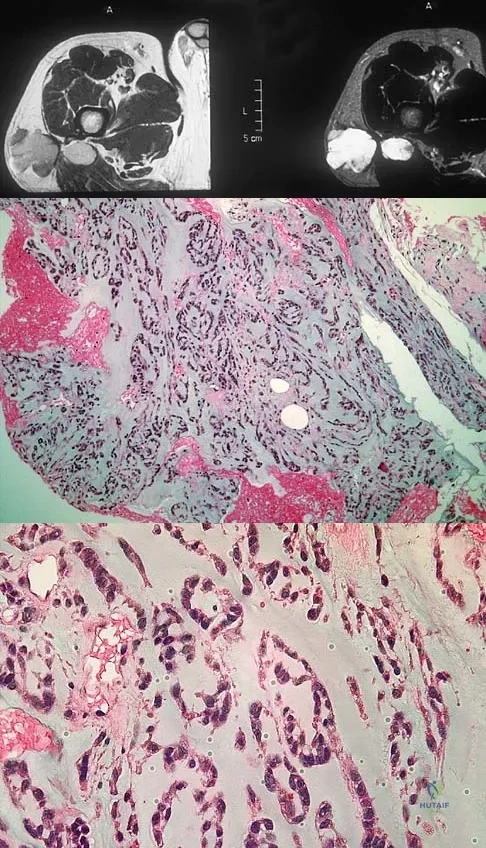

A 75-year-old woman has had severe shoulder pain for the past month. Her medical history includes hypertension and a total nephrectomy for renal cell carcinoma 7 years ago. Radiographs and sagittal MRI scans are shown in Figures 36a through 36d. A bone scan reveals this to be an isolated lesion. Biopsy findings are consistent with metastatic renal cell carcinoma. What is the most appropriate treatment for this patient?

Resection and reconstruction of this very proximal lesion provides the best chance to avoid hardware complications that may be associated with stabilization procedures. Wide resection of isolated renal cell carcinoma metastasis, which presents distant to the nephrectomy, may improve long-term survival. Fuchs B, Trousdale RT, Rock MG: Solitary bony metastasis from renal cell carcinoma: Significance of surgical treatment. Clin Orthop Relat Res 2005;431:187-192.